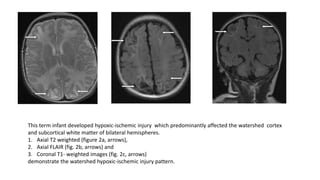

This term infant developed hypoxic-ischemic injury which predominantly affected the watershed cortex

and subcortical white matter of bilateral hemispheres.

1. Axial T2 weighted (figure 2a, arrows),

2. Axial FLAIR (fig. 2b, arrows) and

3. Coronal T1- weighted images (fig. 2c, arrows)

demonstrate the watershed hypoxic-ischemic injury pattern.